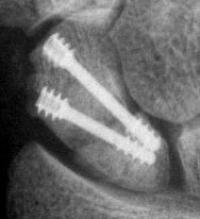

Case 7. This nonunion patient's scaphoid and iliac crest were unusually soft bone.

Click for larger image

After two screws, the fixation was clearly inadequate, so I put a third screw through the graft into the proximal pole. I wasn't sure whether to buy

stock in Herbert screws or Zantac. The fracture healed despite AWOL and no immobilization.